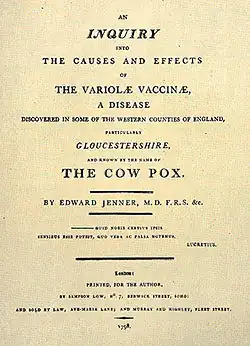

Современники отнеслись к исследованиям Дженнера с осторожностью. Так, в 1798 году Лондонское королевское общество отказалось опубликовать в своих «Трудах» его сочинение «Исследование причин и действие коровьей оспы»[11] с предостережением «не рисковать своей репутацией представлением учёному органу всего, что выглядит таким расходящимся с установившимся знанием»[12], и Дженнеру пришлось за свой счет печатать брошюру, в которой был изложен опыт 25-летних исследований и результаты наблюдений за 23 случаями прививки, включая прививку его сына, 11-месячного Роберта[13].

- Edward Jenner. An Inquiry Into the Causes and Effects of the Variolae Vaccinae, A Disease Discovered in Some of the Western Counties of England, Particularly Gloucestershire, and Known by the Name of the Cow Pox (англ.). — London, 1798.